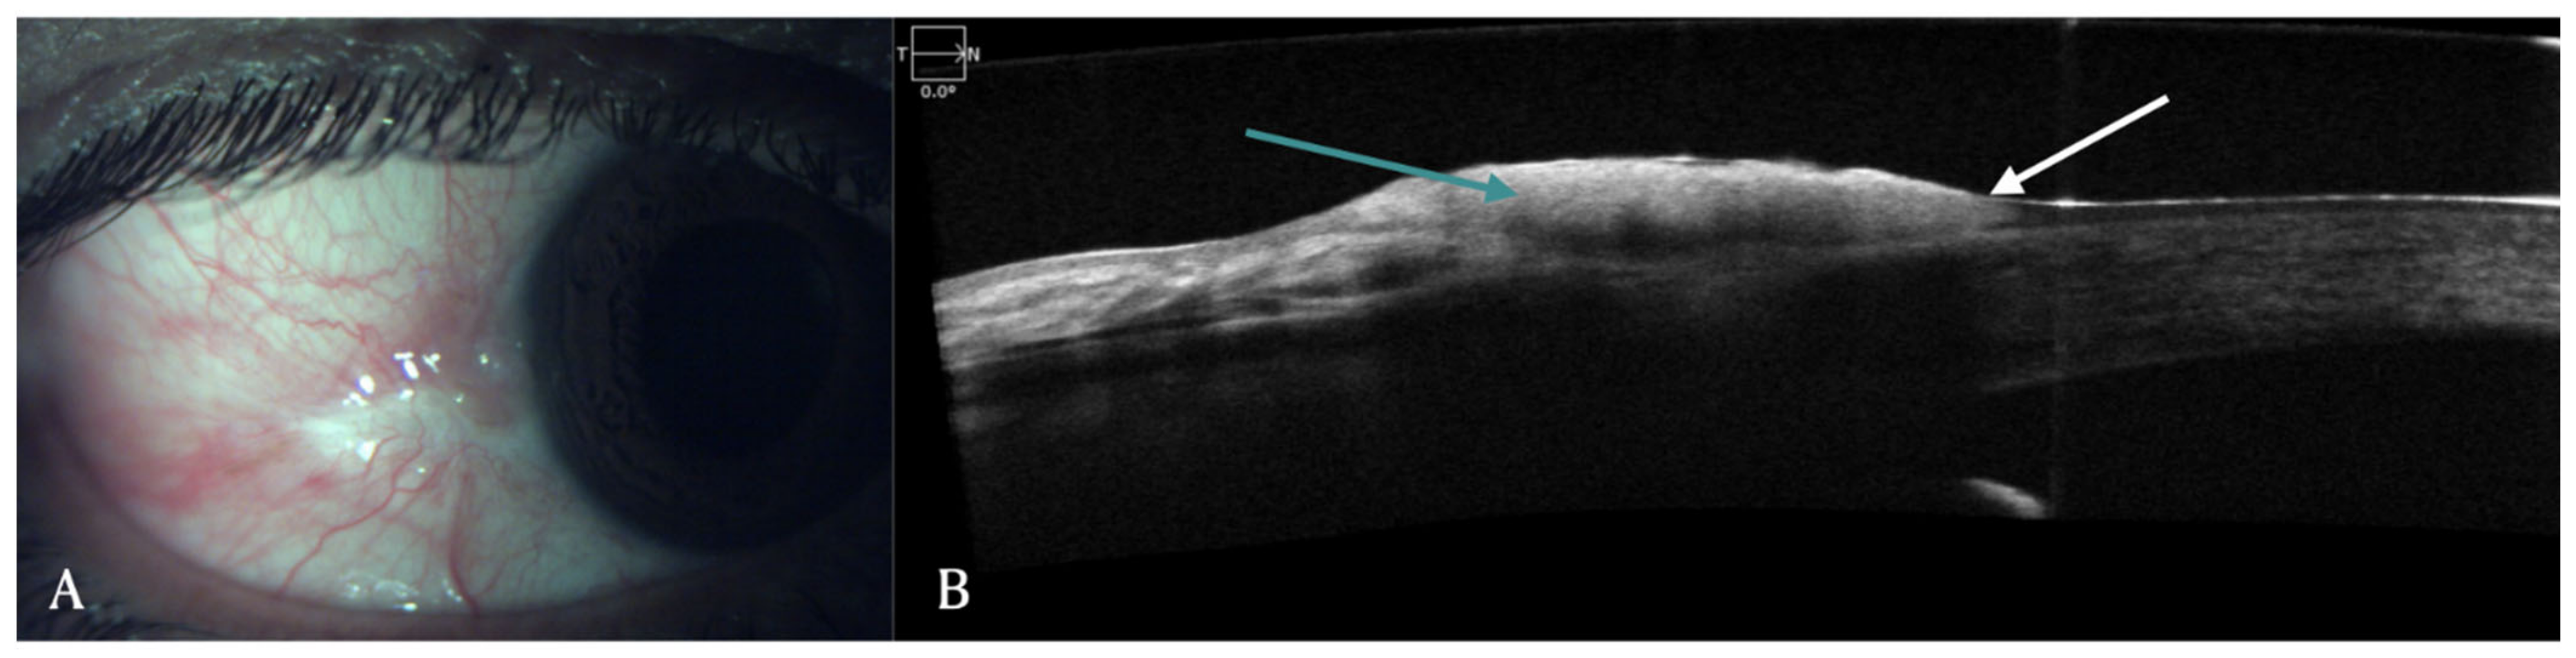

2. Conjunctival Diseases